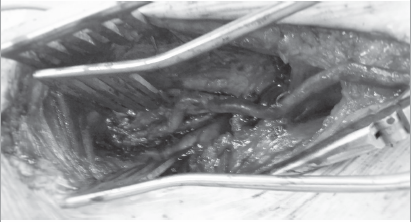

На фиг. 3 - фотоотчет этапа операции, где 9 - большеберцовая кость и волокна мышцы длинного сгибателя пальцев; 1 - передняя большеберцовая артерия (взята на держалку и продольно вскрыта для формирования анастомоза); 4 - фрагмент камбаловидной мышцы (после ее отсечения от большеберцовой кости); 7 - задняя большеберцовая мышца после мобилизации от межостной мембраны.

Рисунок 2. Фотоотчет этапа операции, где 9 ― большеберцовая кость и волокна мышцы длинного сгибателя пальцев, 1 ― передняя большеберцовая артерия (взята на держалку и продольно вскрыта для формирования анастомоза), 2 ― задняя большеберцовая мышца ― поле мобилизации от межостной мембраны, 4 ― фрагмент камбаловидной мышцы (после ее отсечения от большеберцовой кости)